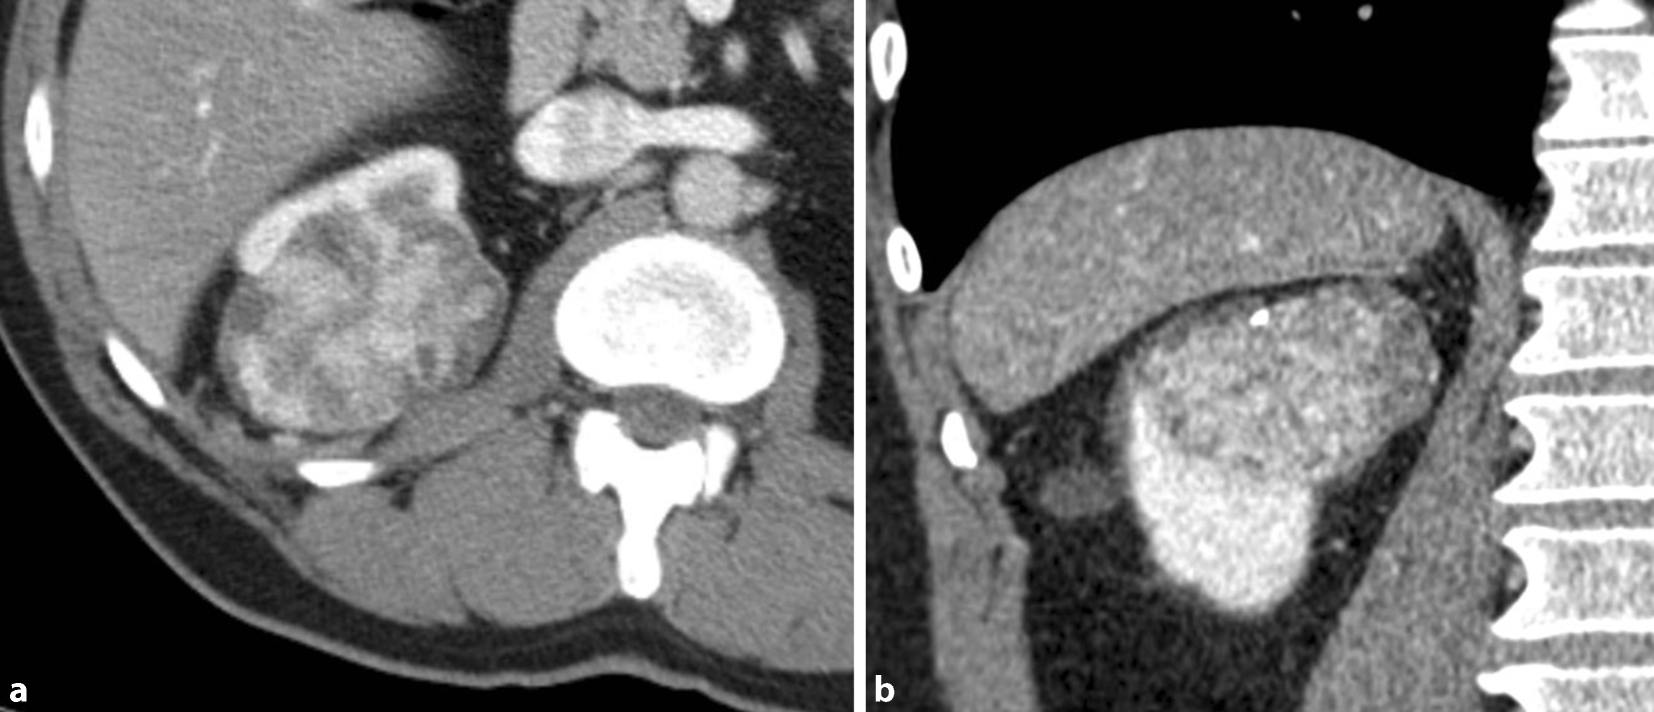

Das Nierenzellkarzinom (Abb. 1) macht je nach Geschlecht ca. 3 % aller malignen Erkrankungen aus. In Europa, Nordamerika und Australien sind die Inzidenzraten höher als in Asien und Afrika. In Europa sind Männer mit einer Inzidenz von ca. 26/100.000 deutlich häufiger als Frauen mit einer Inzidenz von ca. 12/100.000 betroffen. Das mittlere Erkrankungsalter liegt zwischen 60 und 70 Jahren [20]. Als erworbene Risikofaktoren für die Entstehung eines Nierenzellkarzinoms werden hauptsächlich Rauchen, Übergewicht und arterielle Hypertonie beschrieben [21]. In rund 5–8 % der Patienten tritt das Nierenzellkarzinom im Rahmen einer hereditären Störung auf. Die bekanntesten assoziierten Syndrome sind das Von-Hippel-Lindau-Syndrom, das Birt-Hogg-Dubé-Syndrom, tuberöse Sklerose und hereditäres nichtpolypöses kolorektales Karzinom.

Abb. 1

Nierenzellkarzinom

Das Nierenzellkarzinom macht etwa 90 % der malignen Nierentumoren aus und ist eine heterogene Erkrankung. Histologisch dominieren das klarzellige (ca. 80–90 %), das papilläre (Typ I und II, ca. 6–15 %) und das chromophobe (ca. 2–5 %) Karzinom [4].